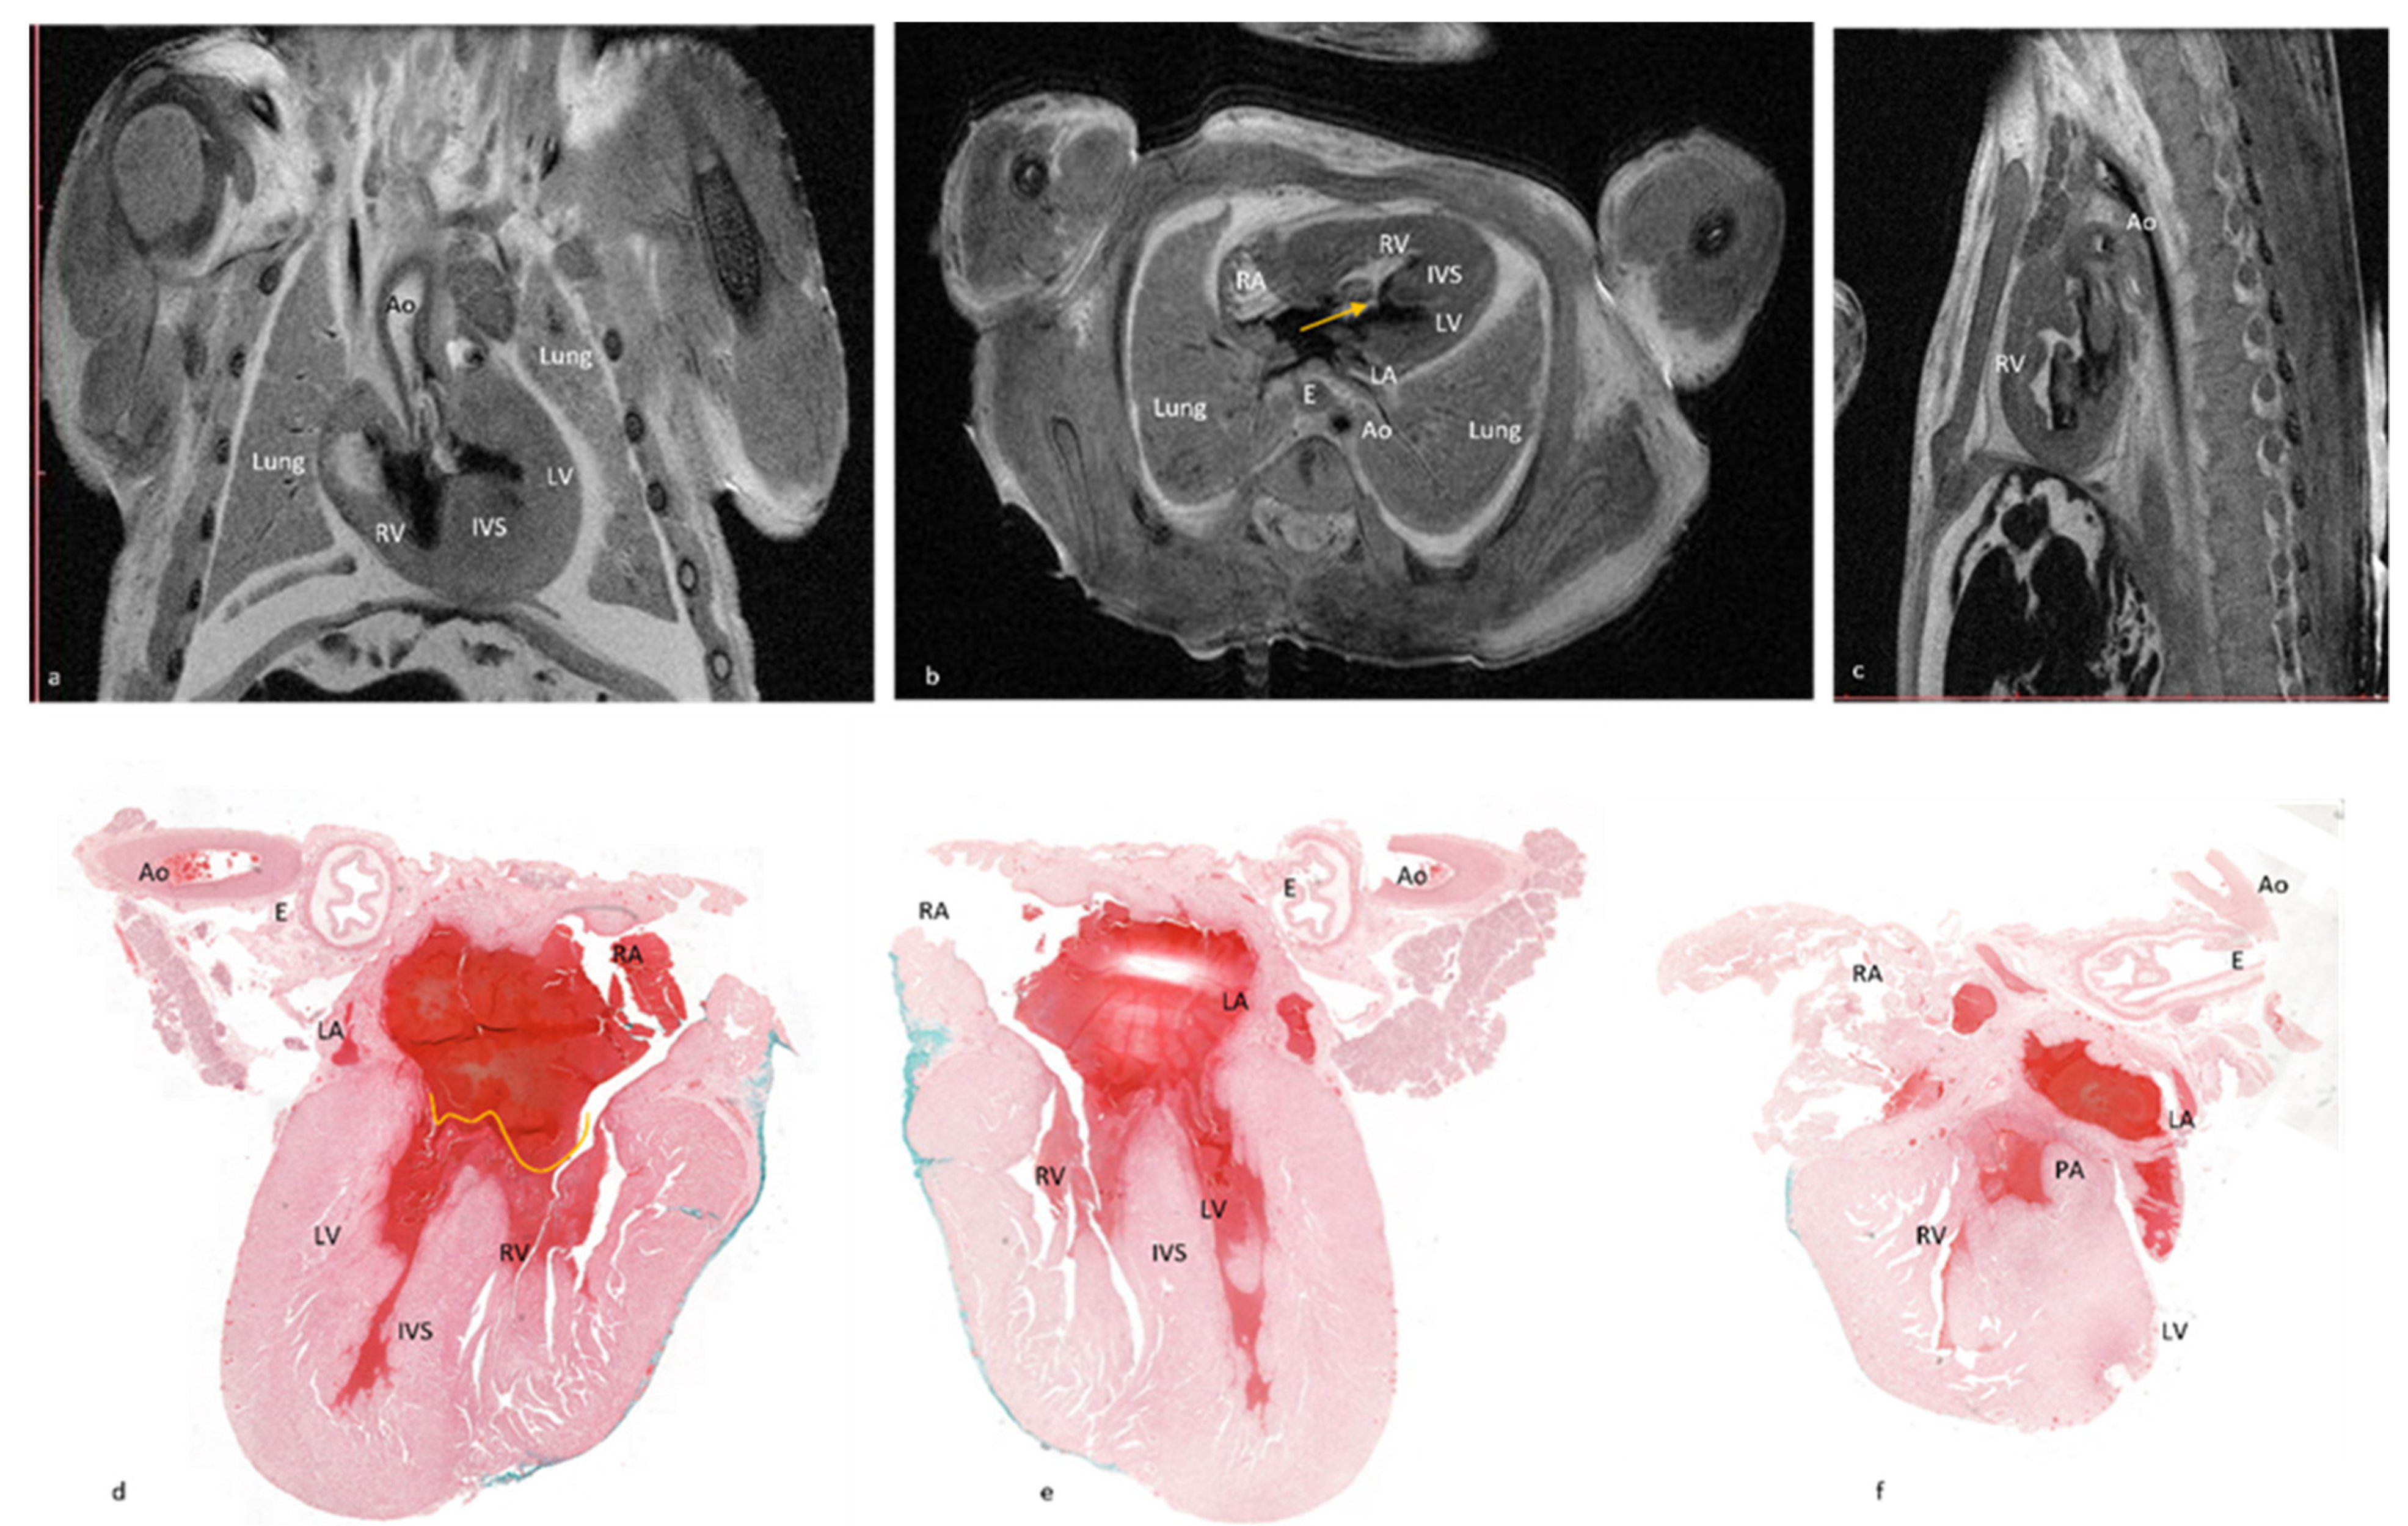

In case No.11, both methods diagnosed the complete atrioventricular canal but pm-MRI also diagnosed a hypoplastic left ventricle as well as an overriding aorta and arterial duct agenesis. Comparative images with observed lesions are depicted in

Figure 5. Additionally, in case No.12, though both methods described most of the lesions, 4CCD failed to describe bilateral ventricular hypertrophy and a ventricular septal defect. Thus, 4CCD overdiagnosed an aortic valve stenosis and tricuspid valve stenosis. Comparative images are presented in

Figure 6. Therefore, as shown in